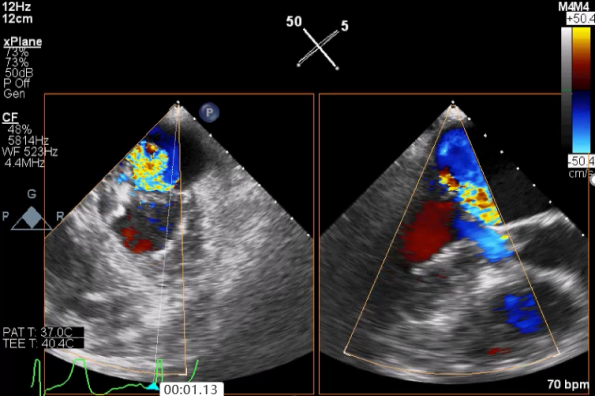

麻醉状态下TEE显示中大量返流MR:

患者麻醉方式采取全麻,建立静脉通路后,穿刺右侧股动脉以及股静脉,预埋ProGlide缝合器,冠脉造影复查提示支架通常。TEE超声指导下经房间隔穿刺后进入左房,送入鞘管,MitraClip调整后顺利到达二尖瓣目标位置,后在X线及食道超声辅助下,使用1枚XTR二尖瓣夹准确夹合二尖瓣A2-P2区,超声即刻测反流面积明显减少,LVOT切面,四腔心切面以及3D下证实夹合组织充分,患者收缩压由术前的108/62mmHg上升至130/72mmHg,左心房压力显著减低,肺静脉多普勒波形由反向恢复正常。手术顺利结束,安返普通病房。

XTR夹子释放,返流明显减少